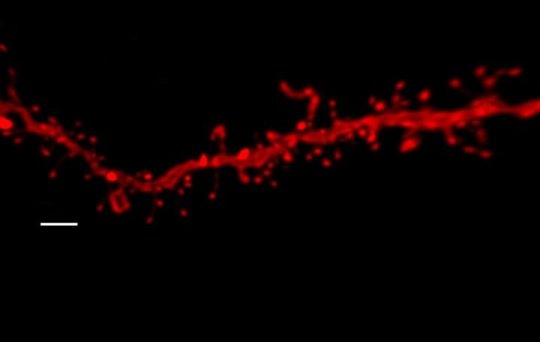

“We have observed that adolescent mice treated with THC and exposed to stress display impaired fear extinction in adulthood. However, this effect was not observed in animals exposed to these same two factors separately,” Fernando Berrendero explains. In addition, the resistance to fear extinction was associated with a decrease in neuronal activity in the basolateral amygdala and the infralimbic prefrontal cortex, suggesting a deregulation in the long term of the circuit that regulates fear.